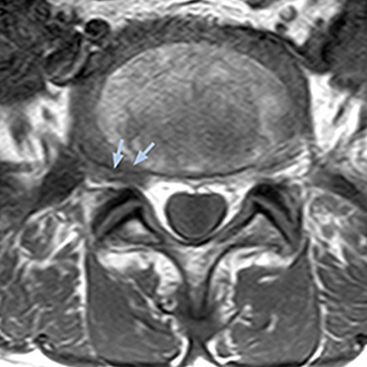

The key concept in MR neurography, Dr. Yabuki stresses, is the ability to directly visualize spinal nerves, versus inferring the presence of pathology indirectly. “Before NerveVIEW, we estimated compression of the nerve by looking for the presence or absence of fat signal on other MR images,” he says.

“For example, in sagittal images, when the presence of fat is observed in the intervertebral foramen, it suggests that there is a margin around the nerve. Similarly, the absence of fat indicates that the nerve is being compressed. So, we used to deduce nerve compression indirectly. With NerveVIEW, however, we can observe the condition of the nerves directly, regardless of the presence or absence of fat. We always prefer such direct observation of anatomy over having to make an inference about it.”

“The intra-luminal signal of veins, especially around the intervertebral space, can be suppressed well with NerveVIEW. As a result, we can easily observe the detailed nerve structure around the posterior ganglion,” he says. “This is why we use 3D NerveVIEW for intraforaminal stenosis and extraforaminal stenosis/herniation (lateral disc herniation). On the other hand, if herniation is suspected to exist inside the dorsal root ganglion (DRG), balanced TFE or ProSet-FFE is applied. NerveVIEW is not suitable for evaluating the median type of herniation.” The SE-EPI DWI-based method for MR neurography works well for large FOV exams like whole-body MRI, but focal examination of nerves is often limited by the attainable spatial resolution (both inplane and slice direction) and geometric distortion. “3D NerveVIEW achieves higher in-plane resolution – close to our other routine spine sequences – and the source images can be used instead of adding a fat-suppressed T2-weighted sequence,” Tanji says.